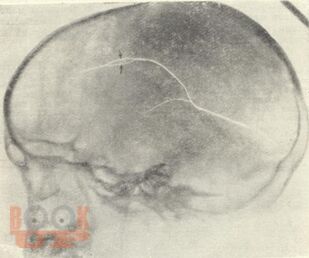

Рентгенодиагностика травматических повреждений черепа и головного мозга

В методических рекомендациях в виде краткого реферата представлены введение, общее понятие о черепно-мозговой травме, частоте таких повреждений и их последствиях. Подробно описана классификация травматических повреждений черепа и головного мозга: 1) закрытая травма без повреждений и с повреждением костей черепа, 2) открытая травма черепа и головного мозга – непроникающая и проникающая. Выделены сотрясение, ушиб и сдавление головного мозга. Основное внимание в методических рекомендациях уделено методике рентгенологического исследования, разновидностям переломов черепа, их дифференциальной диагностике и последствиям черепно-мозговой травме. Приведен краткий литературный список. Методические рекомендации предназначены для интернов, ординаторов, рентгенологов.